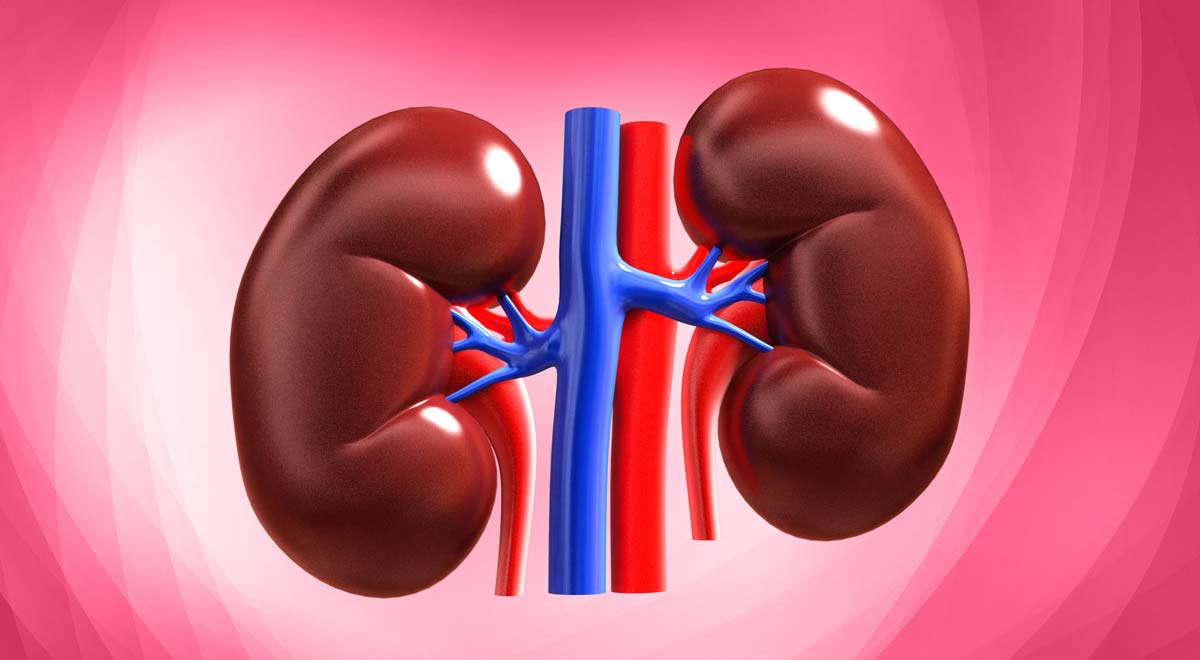

عملکرد کلیه

در طرفین ستون مهره ها و قسمت تحتانی قفسه سینه کلیه قرار دارد. هرکس در حالت طبیعی دارای دو کلیه می باشد. کلیه با عملکرد خود باعث حفظ تعادل در بدن می شود. کلیه دارای وظایفی به شرح ذیل می باشد:

پیوند کلیه

در این روش کلیه ای که متناسب با بدن باشد به بیمار پیوند زده می شود. با این وجود فرد از کلیه ای سالم برخوردار می شود که دیگر نیازی به دیالیز ندارد . امکان موفق نبودن جراحی پیوند کلیه در صورتی که با بدن بیمار سازگار نباشد وجود دارد .